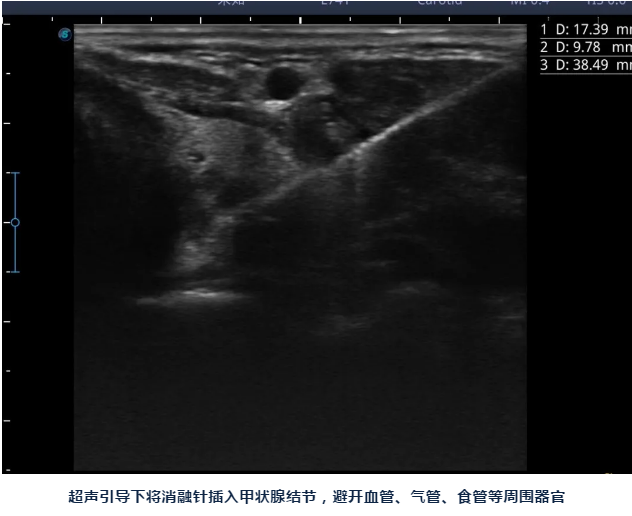

陈主任告诉她:对良性甲状腺结节,现在可以做微创消融治疗,只要局部麻醉,将一根消融针插入结节,通过消融针产生高温就可以将结节灭活,之后结节就会慢慢吸收、缩小。

陈主任说:甲状腺结节消融做完后脖子上只有一个针眼,术后也不影响活动、进食,同时手术是在超声引导下进行,只消融结节,能尽最大限度保护正常甲状腺组织,也可以清楚避开血管、气管、食管、神经等周边组织器官,术后出现声音嘶哑、出血、甲减的几率要小很多。